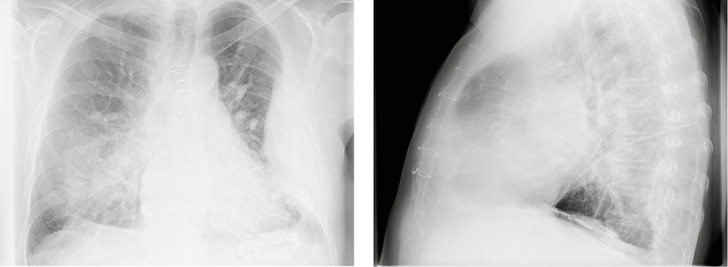

Im Rahmen der Abklärung des chronischen Hustens wurde im Januar 2017 beim Pneumologen eine Röntgen-Untersuchung des Thorax in zwei Ebenen angefertigt. Dabei zeigte sich im p.-a.-Bild in Projektion auf die linke Thoraxwand eine große, in die Lunge hineinragende, gekammerte Raumforderung (  Abb. 1a ). Der linke phrenicocostale Winkel war verklebt. Die rechte Zwerchfellkuppe war nicht glatt begrenzt. Die Lungenhili kamen deutlich vergrößert zur Darstellung. Das Mediastinum war leicht nach links verlagert. Rechtsseitig zeigten sich Kerley-B-Linien. Sternal lagen Cerclagen bei Z.n. Sternotomie. In der seitlichen Aufnahme waren deutliche Pleuraverkalkungen im Bereich der Zwerchfellkuppe erkennbar (  Abb. 1b ).

Im kurz darauf angefertigten Computertomogramm des Thorax zeigten sich massive pleurale Verkalkungen, die teilweise tafelbergartig konfiguriert waren (  Abb. 3 und 4 ). Die Plaques fanden sich lateral auf beiden Thoraxseiten, paravertebral rechts mit krähenfußartigen Ausziehungen sowie an typischer Stelle auf der Zwerchfellkuppe. Links lateral war eine breitflächig gekammerte pleurale Flüssigkeitsansammlung zu sehen. Im nach links verlagerten Mediastinum zeigten sich ein schmaler Mediastinalerguss rechts, eine Aufweitung der Arteria pulmonalis sowie eine Kaudalverlagerung des linken Pulmonalissegments. Der rechte Vorhof war vergrößert. Nebenbefundlich fiel ein Gallenblasenkonkrement auf.

Eine weitere radiologische Kontrolle des Thorax im August zeigte linksseitig eine Verschwartung (  Abb. 6 ).

In dem vorliegenden Fall wurden mit einer Latenz von 44 Jahren nach letzter beruflicher Asbestexposition erstmalig als Zufallsbefund Veränderungen der Pleura festgestellt. Aufgrund der Röntgendiagnostik konnten Verkalkungen und ein Erguss nachgewiesen werden. Darüber hinaus waren beginnende Veränderungen des Lungengerüsts erkennbar. Durch die Punktion des Ergusses konnten die bestehende Herzerkrankung und die rheumatische Arthritis als Ursachen ausgeschlossen werden. Ebenfalls wurde ein Mesotheliom ausgeschlossen. Somit ist eine Asbestpleuritis bei benignem Pleuraerguss wahrscheinlich. Zudem zeigte sich in der Verlaufskontrolle das erneute Auftreten des Ergusses. Die Lungenfunktionsdiagnostik, die bei vorhandenem Erguss durchgeführt wurde, ergab gemäß Leitlinie Spirometrie (2015, s. „Weitere Infos“) noch einen Normalbefund, so dass derzeit kein Therapiebedarf bestand.